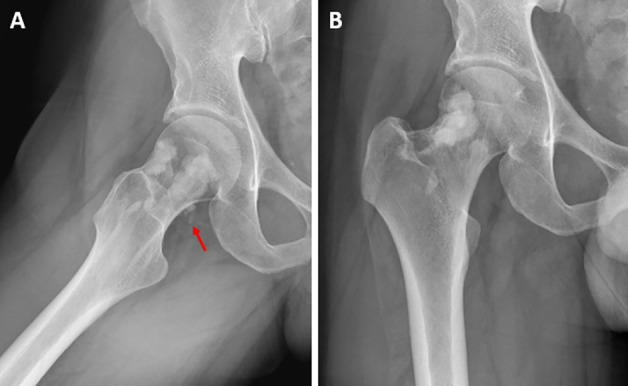

教学要点Melorheostosis 是一种罕见的硬化性骨发育不良,其特点是骨皮质周围和/或骨皮质内侧硬化,导致骨轮廓起伏增厚,类似于 "滴落的蜡烛蜡"。

Teaching point: Melorheostosis is a rare sclerosing bone dysplasia, characterized by sclerosis at the periosteal and/or endosteal side of the cortex, causing undulating thickening of the bony contour resembling "dripping candle wax."